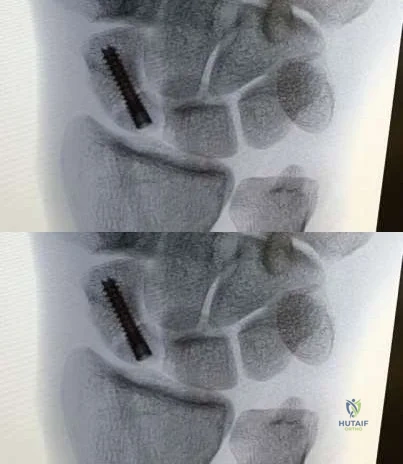

A 24-year-old male falls on an outstretched hand and sustains a fracture of the scaphoid waist. He is evaluated for surgical fixation due to displacement.

Regarding the vascular anatomy of the scaphoid, which of the following is true?

A 30-year-old male presents with dorsal wrist pain and decreased grip strength. Radiographs show sclerosis and partial collapse of the lunate.

According to the Lichtman classification for Kienböck disease, what distinguishes stage IIIA from stage IIIB?

A 32-year-old construction worker presents with central dorsal wrist pain. Radiographs reveal sclerosis and fragmentation of the lunate with a negative ulnar variance of 3 mm, but no carpal collapse.

According to Lichtman's classification of Kienbock's disease, what is the most appropriate surgical intervention?